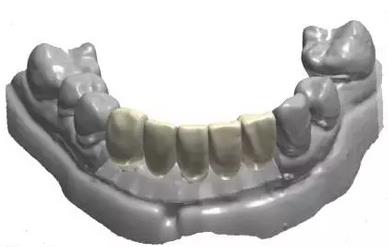

通過3Shape Dental System軟件同期設(shè)計(jì)臨時(shí)冠

手術(shù)導(dǎo)板數(shù)據(jù)發(fā)送至成都登特,通過BEGO打印機(jī)打印出導(dǎo)板,切削出臨時(shí)冠